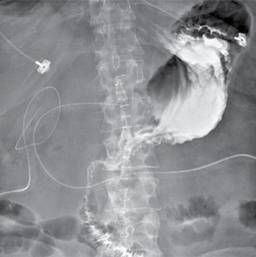

En el postoperatorio inmediato, el paciente ameritó manejo en la Unidad de Cuidados Intensivos por inestabilidad hemodinámica con mejoría paulatina en los días posteriores; retiro de ventilación mecánica invasiva y apoyo aminérgico al tercer día del postoperatorio. Se realizó serie esofagogastroduodenal en el cuarto día postquirúrgico, la cual se reportó con adecuado paso del medio de contraste hacia yeyuno sin evidencia de fuga (Figura 3). Inició la dieta por vía oral, sin complicaciones, el paciente cursaba con gasto seroso mínimo que se retiró en el quinto día postoperatorio, así como disminución progresiva de gasto por duodenostomía hasta su egreso al día siete postoperatorio, por lo que fue egresado tras su mejoría. En seguimiento ambulatorio se retiró duodenostomía en el día 23 del postoperatorio.

Figura 1: Tomografía computarizada con contraste oral e intravenoso. En ventana para pulmón, donde se observa aire libre intraabdominal que diseca los planos del mesenterio.